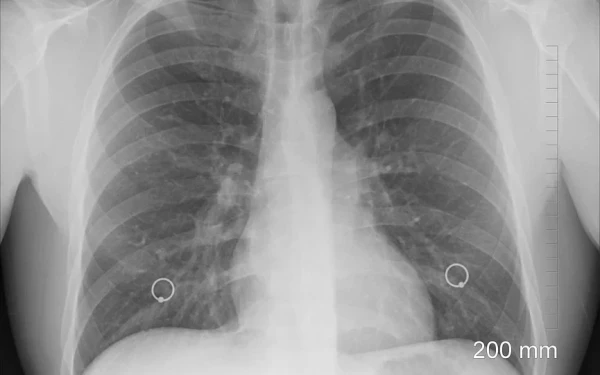

Ειδικότερα για το χολαγγειοκαρκίνωμα, που ήταν και το θέμα της ημερίδας, ειπώθηκε από τον Χειρούργο κ. ’Ιμβριο πως είναι μία σοβαρή περίπτωση καρκίνου και ιδιαίτερα σπάνια, αλλά ολοένα και πιο συχνή. «Συνήθως προσβάλει μέσες ηλικίες, ανθρώπους πάνω από 50 ετών, και στην Ελλάδα οι ασθενείς είναι γύρω στα 62 - 70 έτη», είπε από την πλευρά του. Ο κ. ’Ιμβριος υπογράμμισε πως «δυστυχώς τα συμπτώματα του χολαγγειοκαρκινώματος είναι πολύ ήπια και αυτός είναι ένας λόγος για την επικινδυνότητα του. Σύνηθες σύμπτωμα είναι ο ίκτερος, δηλαδή το κιτρίνισμα στα μάτια και η διάγνωση γίνεται όταν πλέον είναι προχωρημένος».

Για την ίδια μορφή καρκίνου ο κ. Εμμανουηλίδης συμπλήρωσε πως «σήμερα έχουμε τη βελτίωση των απεικονιστικών τεχνικών, άρα μπορεί να διαγνωστεί νωρίτερα. Υπάρχει και βελτίωση των χειρουργικών τεχνικών, επομένως ο χειρουργός είναι πιο αποτελεσματικός. Ακόμη και στις περιπτώσεις που δεν είναι εφικτή η πλήρης θεραπεία υπάρχουν καινούργια φάρμακα ή επεμβατικές τεχνικές που κάνουν τη νόσο να μην είναι τόσο θανατηφόρα όσο ήταν παλιά. Να έχουμε, δηλαδή, μία σημαντική επιμήκυνση της ζωής των ανθρώπων με καλή ποιότητα ζωής».